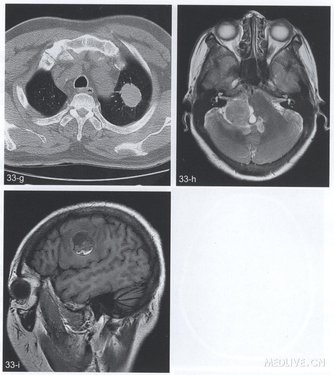

【简要病史】4个病例。例1(图33a~e),女,54岁。乳腺癌术后1年,头痛、言语不清、肢体麻木1周。例2(图33f,g),男,59岁。头痛2个月。例3(图33h),女,50岁。头痛、右听力下降1个月。例4(图33i),右侧颈部恶性黑色素瘤术后2个月头痛。

【CT与MRI所见】例l(图33a),CT平扫显示右侧额叶局限性低密度灶。T1WI(图33b)病变呈圆形,边缘信号较高。FLAIR序列(图33c)幕L脑实质多发高信号灶。增强T1Wl(图33d,e)幕上、下脑实质多发结节状及点状强化灶。例2,轴位增强T1WI(图33f)右丘脑腹内侧结节状明显强化灶。胸部CT(图33g)显示左肺尖结节。例3,轴位T2WI(图33h),右侧桥臂稍高信号肿块。例4,矢状位T1WI(图33i)显示右侧额叶类圆形病变,内见高信号成分。

【手术后病理诊断】例1,乳腺癌脑实质多发转移。例2,细支气管肺泡癌右侧丘脑转移。例3,右侧桥臂转移瘤(来源不明)。例4,右额叶恶性黑色素瘤转移。